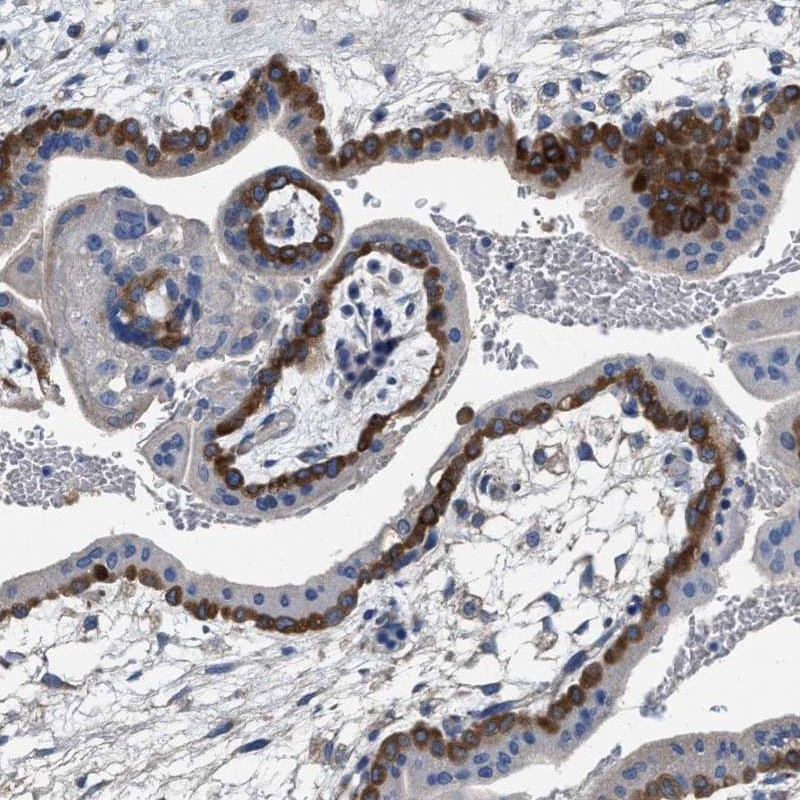

Immunohistochemistry analysis in human placenta and prostate tissues using Anti-PEG10 antibody. Corresponding PEG10 RNA-seq data are presented for the same tissues.